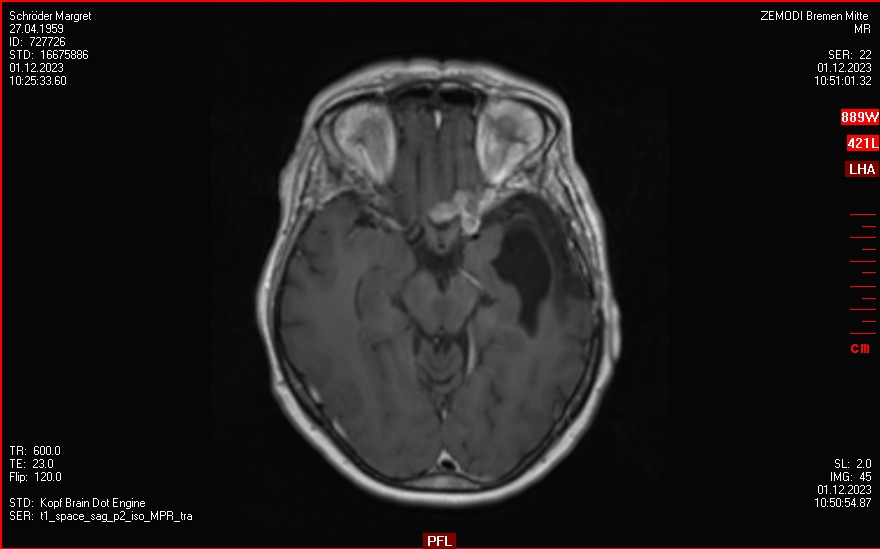

bis Mitte 2023

Regelmäßige Kontrollen, kleine Rezidiv-Funde aber keine Empfehlung für eine Behandlung.